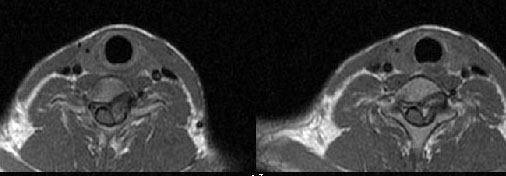

男24岁因一年来感头昏,查体四肢肌力及感觉无异常。颈椎dr未见异常,mri发现c7水平段椎管内左侧占位。患者于7年前有车祸伤病史(但是未检查,自述无异常)。请讨论是否是机化血肿或骨折片,能除外是肿瘤?

椎管内骨性肿块,与第7颈椎左下关节突关系密切,向椎管内生长,第7颈椎椎体左后缘受压变形,边缘可见硬化边,与肿块间间隙清晰。mri扫描肿块内可见骨髓信号,考虑骨软骨瘤可能性大。